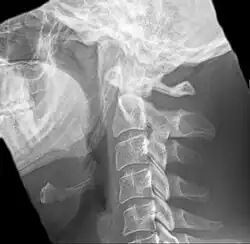

Radiograph, lateral view showing elongated stylohyoid process and stylohyoid ligament ossification -

Radiograph, lateral view showing joint-like formation in ossified stylohyoid ligament -

Imaging is important and is diagnostic. Visualizing the styloid process on a CT scan with 3D reconstruction is the suggested imaging technique.[13] The enlarged styloid may be visible on an orthopantogram or a lateral soft tissue X ray of the neck.